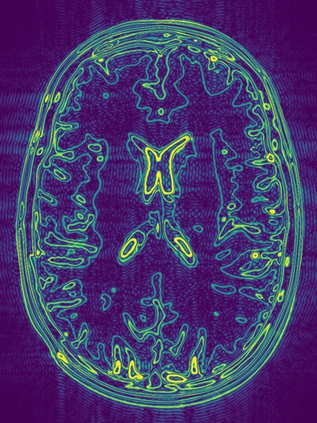

Implicit neural representations (INRs) have emerged as a powerful tool for solving inverse problems in computer vision and computational imaging. INRs represent images as continuous domain functions realized by a neural network taking spatial coordinates as inputs. However, unlike traditional pixel representations, little is known about the sample complexity of estimating images using INRs in the context of linear inverse problems. Towards this end, we study the sampling requirements for recovery of a continuous domain image from its low-pass Fourier coefficients by fitting a single hidden-layer INR with ReLU activation and a Fourier features layer using a generalized form of weight decay regularization. Our key insight is to relate minimizers of this non-convex parameter space optimization problem to minimizers of a convex penalty defined over an infinite-dimensional space of measures. We identify a sufficient number of samples for which an image realized by a width-1 INR is exactly recoverable by solving the INR training problem, and give a conjecture for the general width-$W$ case. To validate our theory, we empirically assess the probability of achieving exact recovery of images realized by low-width single hidden-layer INRs, and illustrate the performance of INR on super-resolution recovery of more realistic continuous domain phantom images.